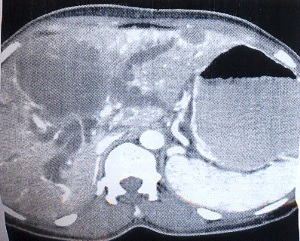

Carcinoma of the gallbladder is the most common malignancy of the biliary tract. Although adenocarcinomas account for more than 90% of gallbladder cancers, the incidence of adenosquamous carcinomas (ASCs) is only approximately 5%. ASCs have aggressive biological behavior due to their potential for direct extension into the liver and neighboring structures like stomach, duodenum, and transverse colon. In most cases, the disease would have advanced at the time of diagnosis and the prognosis might be dismal when compared to ordinary adenocarcinoma of the gallbladder. We present here a rare case of ASC of gallbladder in a 59-yr-old female who presented with right upper abdominal pain.